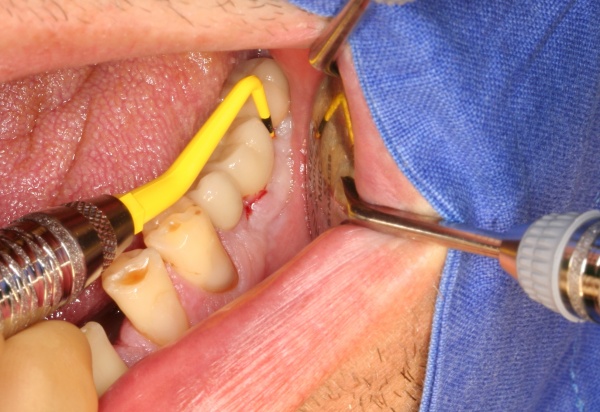

In der präimplantologisch chirurgischen Phase ist darauf zu achten, dass möglichst viel Knochen bei einer Osteotomie erhalten bleibt. Die labiale/bukkale Knochenlamelle genießt besonderen Schutz. Häufig macht es Sinn, den Zeitpunkt einer Extraktion bzw. einer Osteotomie sowie deren Technik mit dem implantierenden Kollegen abzustimmen oder diese auch durch den Implanteur selbst vornehmen zu lassen (Abb. 4).

Eine weichgewebschirurgische Vorbereitung des zukünftigen Implantatlagers bereits zu diesem Zeitpunkt ist häufig ratsam. Dazu gehört unter anderem wie in diesem Bildbeispiel die Verbreiterung der Zone keratinisierter Gingiva. Eine gedeckte Einheilung des Implantates wird somit wahrscheinlicher. Therapeutisch kompliziertere Eingriffe nach der Freilegung oder sogar erst nach prothetischer Versorgung werden vermieden (Abb. 5a/b).